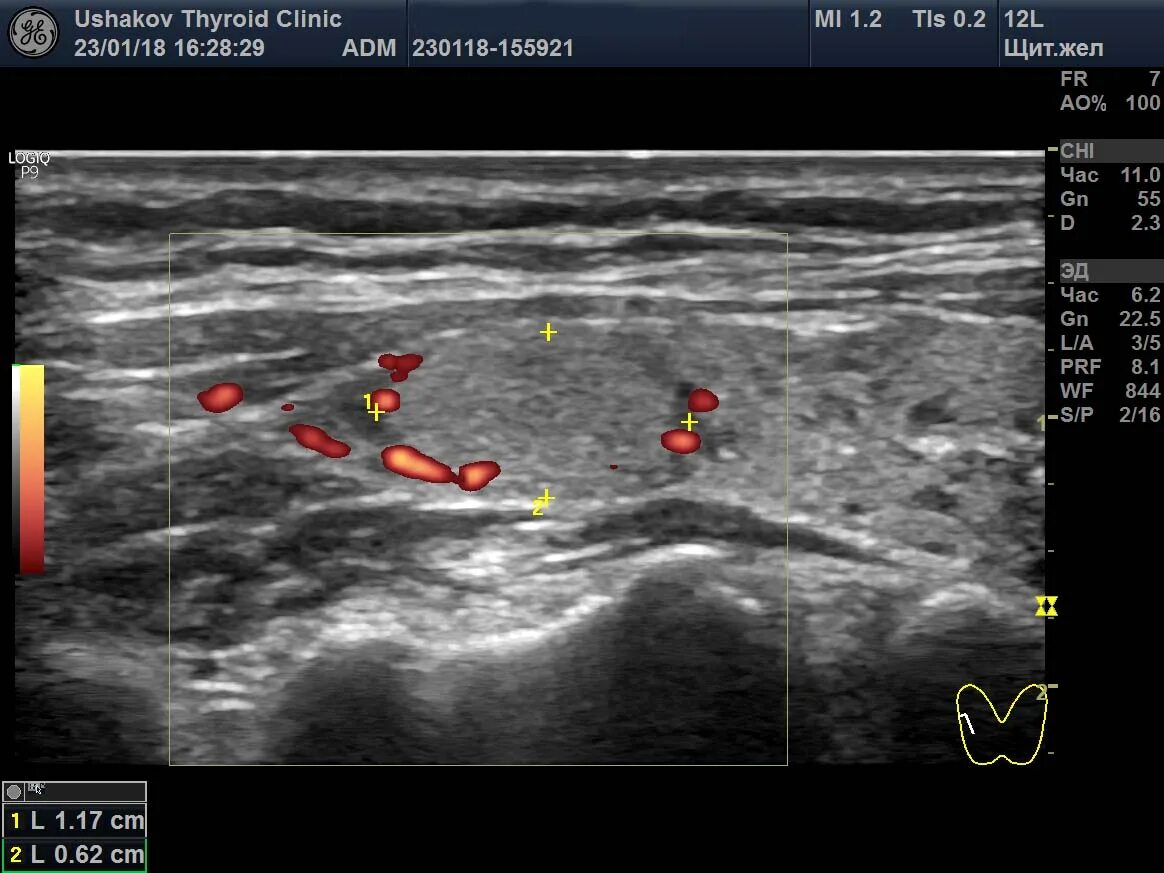

Локусы при цдк что это